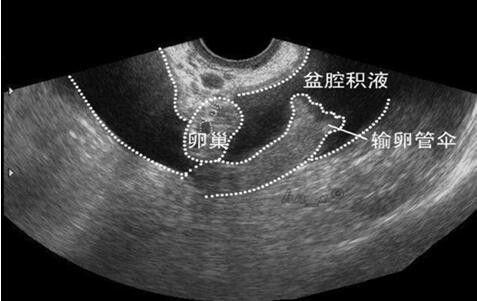

盆腔积液究竟是什么呢?长沙精诚在解剖上,盆腔处于腹腔最低的部位,因此当盆腹腔内脏器有渗出液、漏出液或出血时,液体首先积聚在盆腔最低部位,从而形成盆腔积液。其实,盆腔积液是一种临床表现,而不是一种独立的疾病,确切地说这仅是影像学对盆腔内液体的一种描述。而盆腔炎是指女性内生殖器及其周围的炎症,常可在B超检查时发现有盆腔积液,那么,是不是有盆腔积液就一定是有盆腔炎呢?

答案当然是NO!盆腔积液有生理性和病理性之分。每个女性的一个月经周期中,有两个时间段可能会出现生理性盆腔积液,一是每月排卵后,排出的卵泡液、输卵管内壁柱状上皮细胞分泌的输卵管液可以短暂积聚于盆腔最低部;二是经期以后,宫腔里的部分经血倒流至盆腔内,或近期盆腔内腹膜充血渗出等。所以女性朋友经常发现在经期或排卵期容易出现盆腔积液,这属于生理现象。超声检查积液深度一般在1~2cm,通常无明显症状,无需特殊处理,不用太紧张。

盆腔内腹膜急性炎症,导致炎性渗出增加,腹膜自行吸收能力减弱。患者通常伴有腹痛、发热、实验室检查示白细胞及中性粒细胞总数/比例升高。B超可见盆腔或/和输卵管积液,妇科检查发现宫体、附件区压痛,尤其是手术中看到,或阴道后穹窿穿刺出脓性液体时,可以确定急性盆腔炎的诊断;如果B超发现盆腔反复积液,或附件区不均质包块或囊肿,患者有不孕、宫外孕、慢性盆腔疼痛病史,妇检扪及子宫体后倾,附件增厚或包块,则盆腔炎性疾病后遗症诊断成立。一旦诊断为急性盆腔炎,需规范地使用抗生素治疗。

5、宫外孕、卵巢囊肿破裂、黄体破裂导致盆腔内出血,B超提示多量盆腔积液。

患者有急腹症表现,如腹痛,腹部压痛阳性、反跳痛阳性,如果超声示盆腔积液透声差,则常为血块,此时可行后穹窿穿刺,如抽吸出不凝血,则证明腹腔内出血。